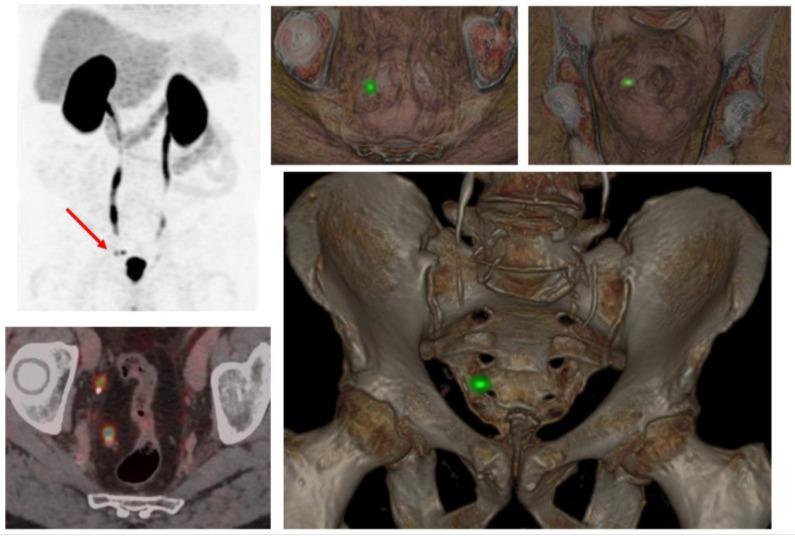

Prostate-specific membrane antigen positron emission tomography/computed tomography (PSMA-PET/CT) has emerged as a game-changing imaging modality in prostate cancer, offering superior sensitivity and specificity compared to conventional imaging techniques. Its increasing adoption has significantly influenced radiotherapy decision-making, yet its true clinical impact remains under investigation. This narrative review explores the role of PSMA-PET/CT in guiding radiotherapy decisions across different clinical scenarios, from primary treatment planning to biochemical recurrence and oligometastatic disease. We assess its impact on target delineation, treatment modifications, and overall patient management while addressing existing knowledge gaps.

前列腺特异性膜抗原正电子发射断层扫描/计算机断层扫描(PSMA-PET/CT)已成为前列腺癌领域一项具有变革性的成像模态,与传统成像技术相比,具有更高的敏感性和特异性。其应用的日益广泛显著影响了放疗决策,但它的真正临床影响仍在研究中。这篇叙述性综述探讨了PSMA-PET/CT在不同临床场景中指导放疗决策的作用,从初始治疗计划到生化复发和寡转移疾病。我们在解决现有知识空白的同时,评估其对靶区勾画、治疗调整和整体患者管理的影响。